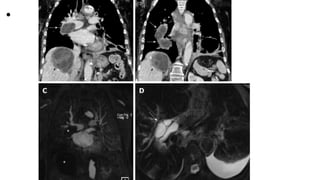

• A 48-year old male with mediastinal hydatid cyst presented with acute

chest pain. A: Axial image of enhanced computed tomography

angiogram shows a complex cystic lesion with thick wall (white arrows)

that is predominately located in the left side of the posterior

mediastinum with evidence small calcifications at the periphery of the

lesions at the site of abutment with descending thoracic aorta. There is

adjacent pleural effusion (white asterisk) and enhancing left lower lobe

atelectasis (white asterisk); B, C: Axial and coronal T2 weighted images

show a complex cystic lesion with thick dark rim (arrows) abutting the

descending thoracic aorta with multiple peripheral daughter cysts of

higher signal intensity compared to the intermediately hyperintenese

matrix of the mother cyst. Magnetic resonance imaging findings are

highly suggestive of hydatid cyst, likely primary given absence of

evidence of lung and liver hydatid disease.

• An 82-year-old female with pulmonary artery hydatid cyst embolism

presented with shortness of breath. A, B: Coronal images of enhanced

computed tomography scan show right main pulmonary artery

intraluminal cystic filling defects causing expansion and near occlusion

of the artery with extension into the right interlobar pulmonary artery

(white arrows). There is hepatic hydatid cyst with internal septation and

daughter cysts and scattered wall calcifications (black arrows); C:

Coronal image of T1 weighted magnetic resonance angiography

confirms the presence of filling defect of low signal intensity within the

right pulmonary artery and low signal intensity liver lesion (asterisks)

with no evidence of contrast enhancement; D: Axial T2 weighted image

with fat saturation shows right main pulmonary artery intra-luminal

cystic filling defects of high signal intensity with septations suggestive of

daughter cysts (arrow). Left pleural effusion is noted.

• Pericardial hydatid cyst. A, B: Axial and coronal

contrast enhanced computed tomography images

show a partially peripherally calcified cystic lesion

(white arrows) along the inferior aspect of the

heart and within the pericardial sac (dashed

arrows) with mild mass effect and displacement of

the right ventricle (black arrow). Small pleural

effusions and ascites are shown (asterisks).